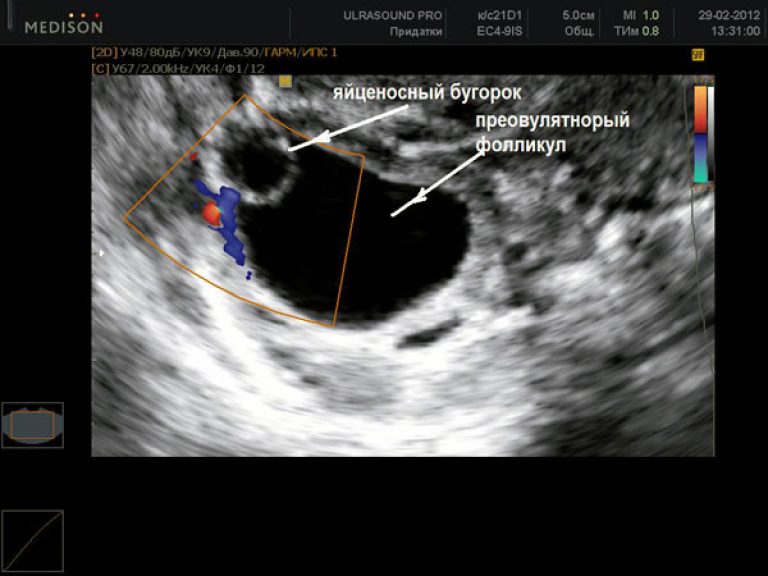

Ультразвуковая диагностика может быть использована для визуализации яичников и фолликулов, содержащих зрелые яйцеклетки. Этот метод более точный, но требует посещения врача и проведения ультразвукового исследования. Ультразвуковая диагностика позволяет определить точное время овуляции и точное количество фолликулов.